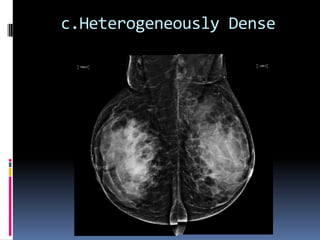

 c.The breasts are heterogeneously dense, which may

obscure small masses

c.Heterogeneously Dense